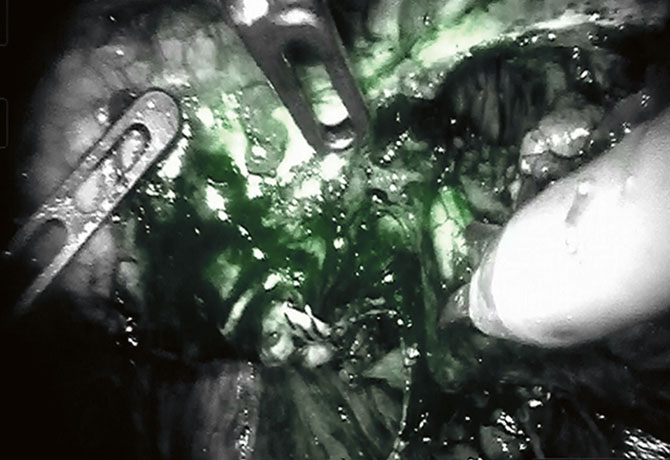

A robotic approach would allow for optimal operating field magnification and a high level of precision to identify the selective arterial branches feeding the lesion, utilizing both intraoperative ultrasound Doppler and immunofluorescence vision.

During the operation, the main renal artery, followed by the large aberrant branches, was dissected until the large aneurysm and surrounding vasculature were identified. Utilizing near-infrared imaging and immunofluorescence guidance, Dr. Badani sequentially identified each branch artery and clipped only the feeding vessels to the lesion. Then, as in a typical robotic partial nephrectomy scenario, he utilized his FAST (First Assistant Sparing Technique) approach, removing the lesion without any warm ischemia time. Estimated blood loss was less than 25 cc, and the patient was discharged after an overnight stay without compromise to her renal function.

According to Dr. Badani, this surgery is an excellent example of how experience with advanced imaging technologies during robotic partial nephrectomy can be utilized in many different ways in a safe and effective manner. He explains, “During robotic kidney cancer surgery, we routinely utilize a picture-in-picture video display of the operative field and real-time ultrasound to delineate the tumor and margins. Additionally, we toggle between a traditional white-light view of the operative field and a near-infrared view to directly visualize active blood flow and regional ischemia based on selective artery clamping. Both of these techniques, refined from experience with robotic partial nephrectomy, were utilized to treat this renal aneurysm, contributing to an excellent outcome.”